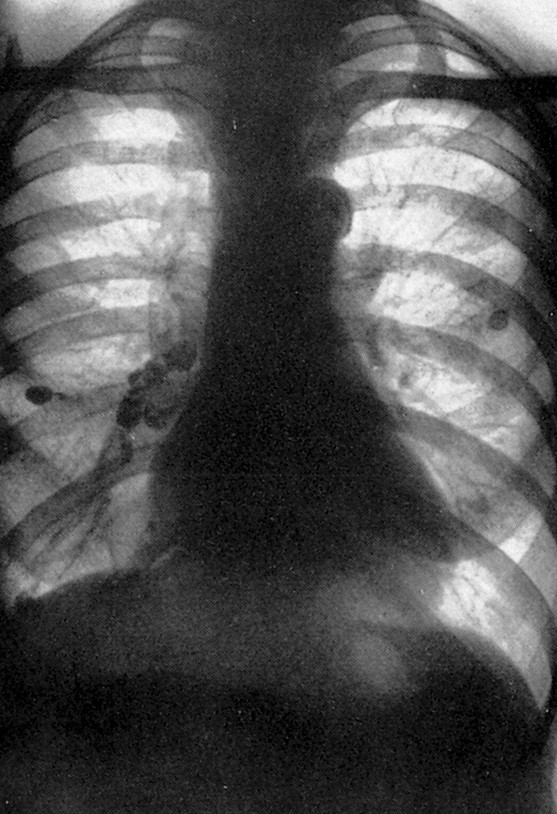

Tuberkulose: Röntgenbild

Fallbeispiel einer Lungentuberkulose im Röntgenbild: Die dunklen Flecke kennzeichnen die verkalkten Lymphknoten.